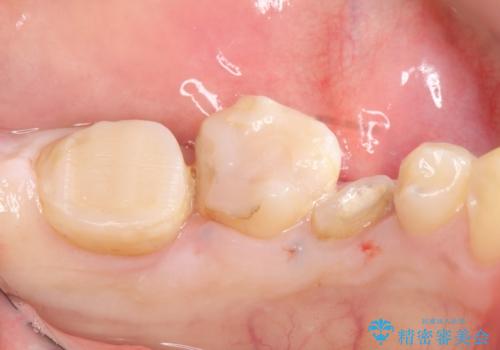

- 左下の奥歯がズキズキ痛むので診て欲しいといらっしゃった方の症例です。他院では5番目と7番目の歯を抜歯してインプラントと言われたが、出来れば歯を残したいとのことでした。

痛みの原因は6番目の虫歯であること、5番目、6番目の歯は歯茎より深い虫歯であり現状では保存が難しいことを説明した上で、歯を挺出させる部分矯正と歯茎を下げる歯周外科を行いました。

手術後歯茎の治癒を待ち、オールセラミッククラウンによる補綴を行いました。